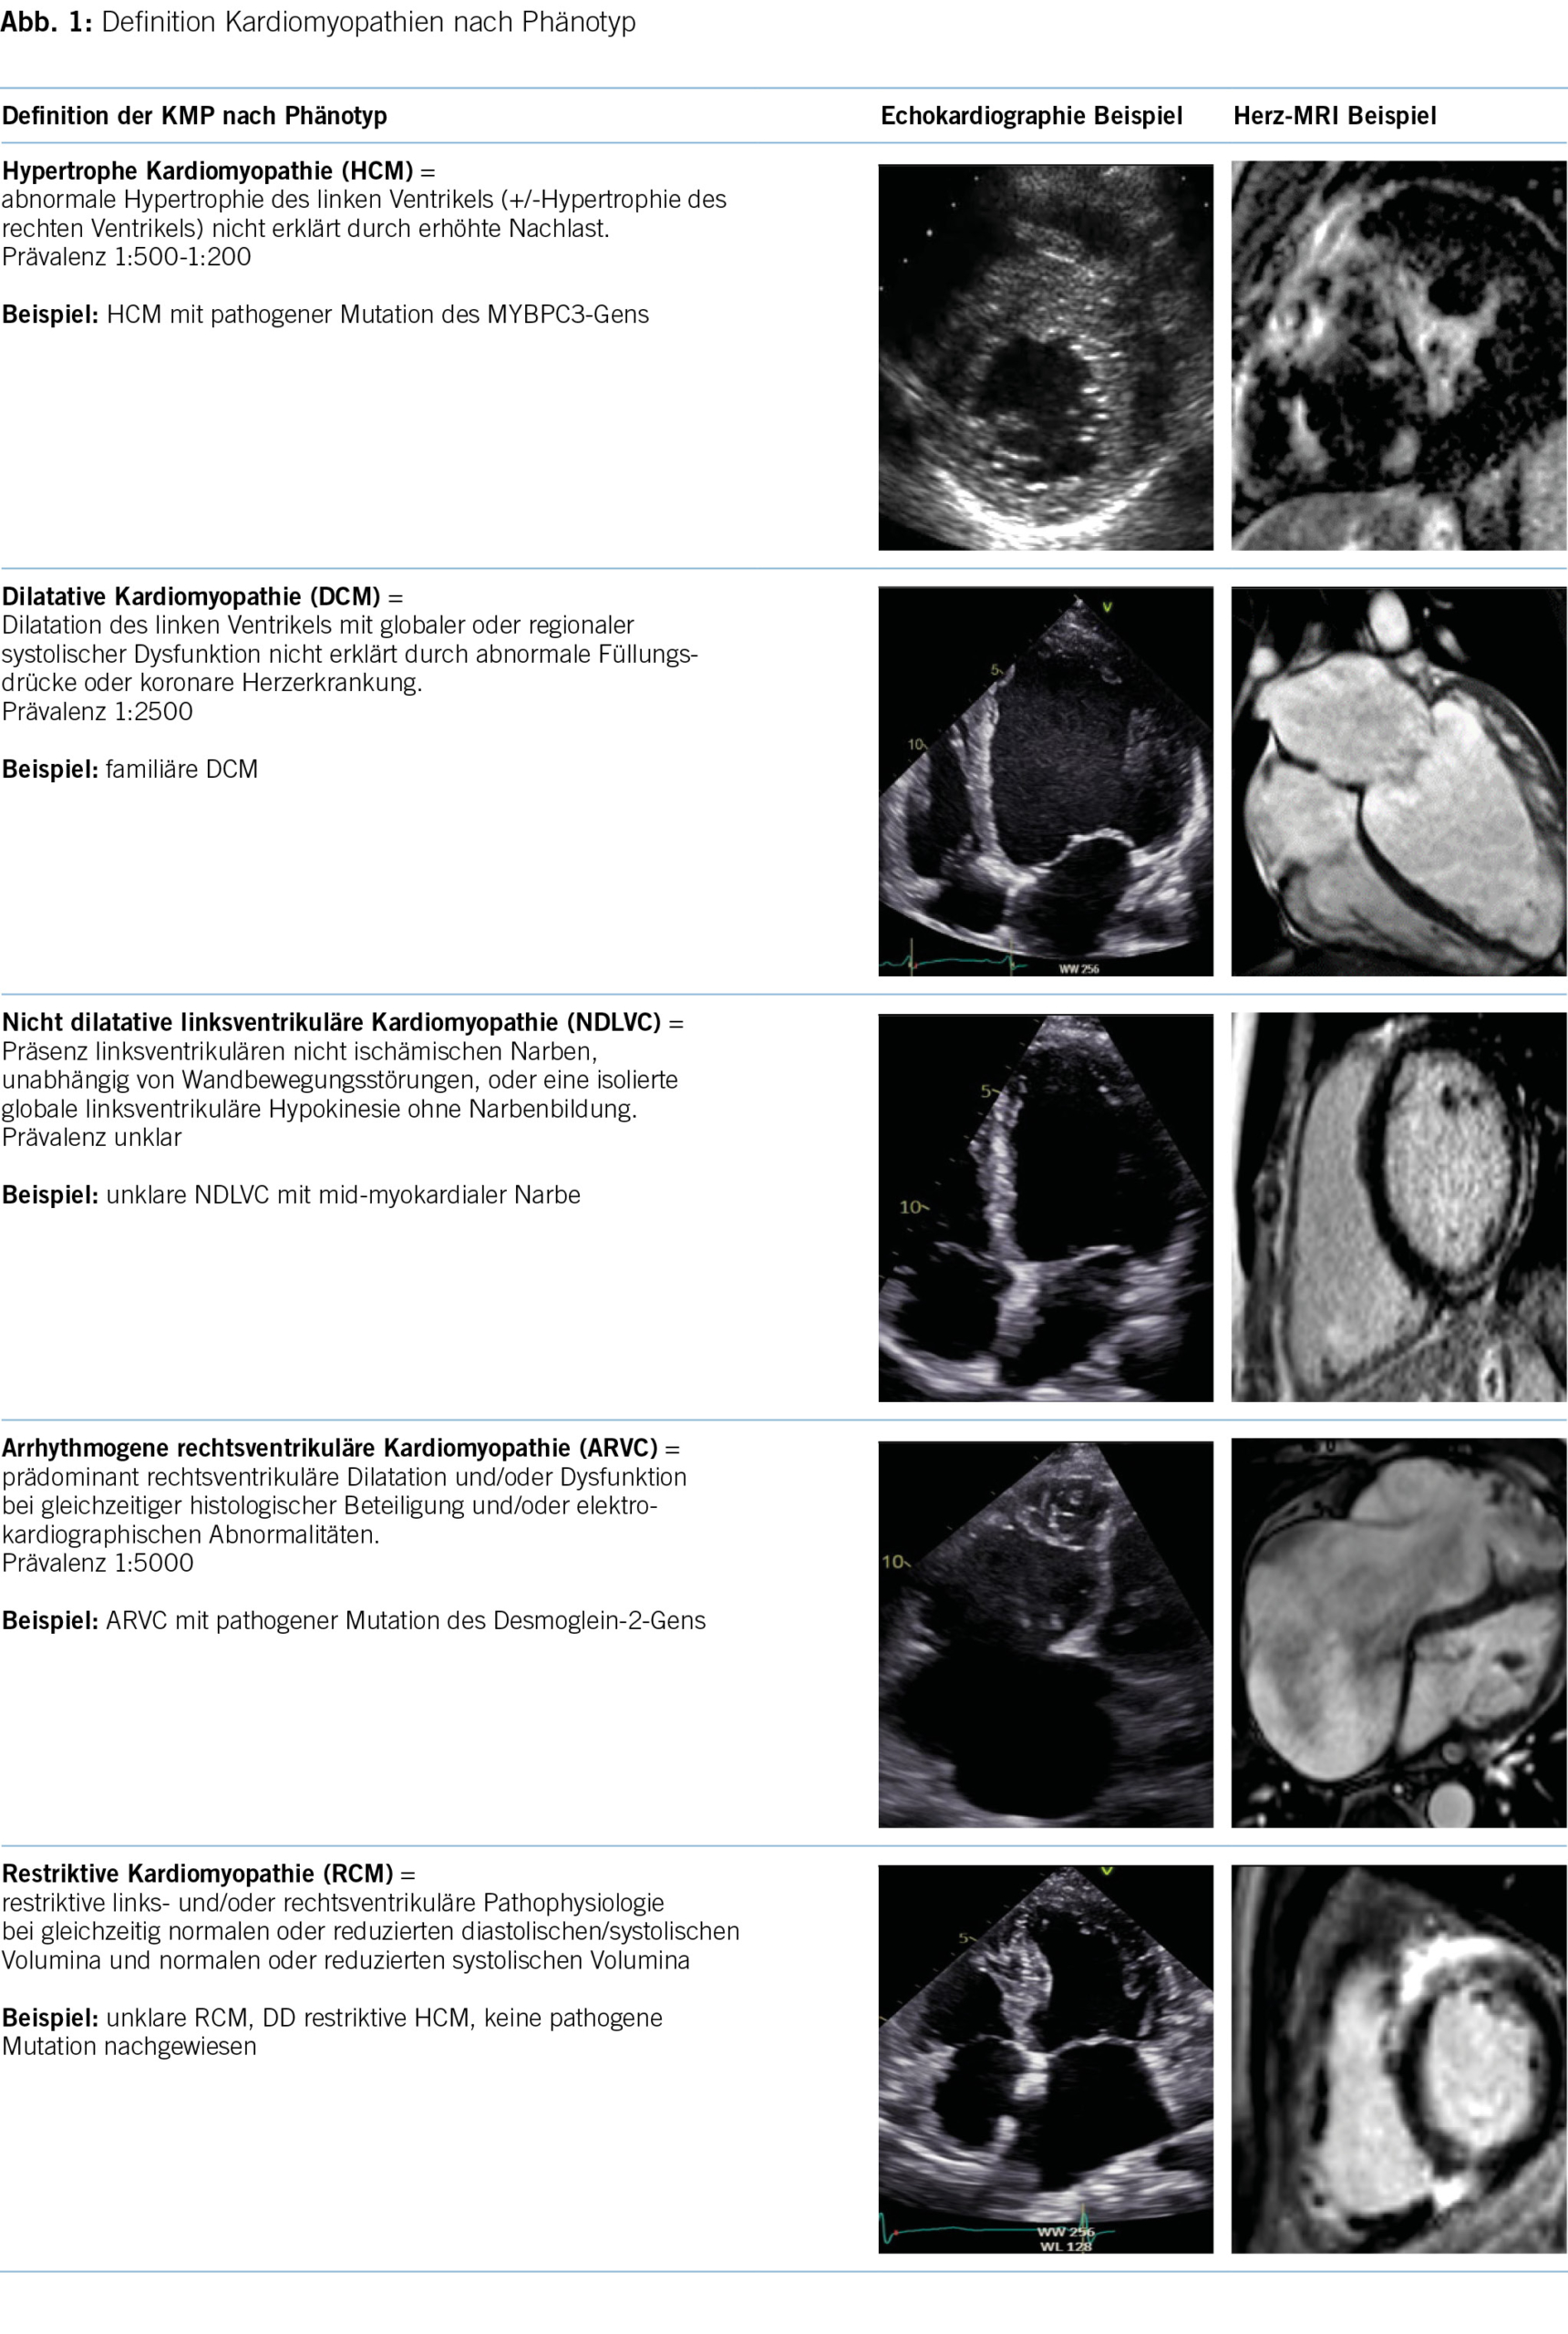

Die Kernaussage der 2023 KMP-Leitlinien besteht vor allem darin, dass bei den behandelnden Ärzten ein sogenanntes cardiomyopathy mindset entwickelt wird und die Ärzte sich nicht nur auf den morphologischen Phänotyp konzentrieren, sondern am Anfang der Patient mit seiner klinischen Präsentation steht (5). Im Rahmen der initialen Abklärung sollen dann auch die differentialdiagnostischen Überlegungen im Zentrum stehen, denn die korrekte Diagnose hat mittlerweile immer mehr Implikationen für die Prognose und therapeutischen Optionen der Patienten und deren Familien. Die ESC 2023 KMP-Leitlinie integriert die bestehenden vier Phänotypen und erweitert sie um einen neuen, fünften Phänotyp namens «nichtdilatierte linksventrikuläre Kardiomyopathie» (NDLVC). Diese Kategorie umfasst Patienten mit isolierter linksventrikulärer Dysfunktion ohne Narbenbildung sowie Patienten mit nicht ischämischer Narbenbildung, unabhängig von einer systolischen Dysfunktion. Dadurch wird ermöglicht, Phänotypen zu berücksichtigen, die trotz Vorliegen einer Myokarderkrankung nicht den Definitionen der anderen Klassen entsprechen (Abbildung 1). Eine wichtige Änderung bei der Einteilung der KMP ist die Beibehaltung des Phänotyps «ARVC», um die ursprüngliche Definition zu beschreiben, bei der die Dilatation des Ventrikels und/oder Wandbewegungsstörungen hauptsächlich auf den rechten Ventrikel beschränkt sind, mit oder ohne Beteiligung des linken Ventrikels (6). Die Verwendung des Sammelbegriffs «arrhythmogene KMP (ACM)» wird nicht anerkannt, und bei einer überwiegenden linksventrikulären Erkrankung sollen die Empfehlungen für NDLVC angewendet werden.

Eine weitere Änderung ist die Abschaffung des Begriffes «non-compaction KMP» als eigenständige KMP. Angesichts des Mangels an morphometrischen Beweisen für ventrikuläre Verdichtung beim Menschen wird der Begriff «Hypertrabekulierung» anstelle von LVNC empfohlen, insbesondere wenn das Phänomen reversibel ist oder klar im Erwachsenenalter auftritt (7, 8). Hinzu kommt, dass sowohl die phänotypische als auch genetische Überlappung mit der DCM und HCM substanziell ist (9). In diesem Zusammenhang bleibt zu erwähnen, dass auch innerhalb derselben Familie mit sehr ähnlichem genetischen Hintergrund verschiedene KMP-Phänotypen auftreten können (10). Dies wird aktuell weiter untersucht, und man vermutet epigenetische wie auch Umweltfaktoren, die jeweils für die Ausbildung der jeweiligen Phänotypen verantwortlich sind. Ebenfalls kann der Krankheitsverlauf bei einem einzelnen Patienten eine Entwicklung von einem KMP-Phänotyp zu einem anderen einschliessen. Die Arbeitsgruppe schlägt einen Ansatz für die Krankheitsnomenklatur und Diagnose vor, der auf dem vorherrschenden kardialen Phänotyp bei der Präsentation basiert. Dennoch ist der Genotyp wichtig für die diagnostische Abklärung, Therapieentscheidungen und Nachsorge. Obwohl die genetischen KMP der Schwerpunkt der neuen Leitlinien sind, wird weiterhin ein systematischer Ansatz ausgehend vom morpho-funktionellem Phänotyp bis zu Erreichen einer präzisen Diagnostik vorgeschlagen. Dabei werden auch nicht genetische KMP, wie zum Beispiel entzündlich, toxisch und multisystemisch, berücksichtigt. Abbildung 2 bietet einen Überblick über mögliche Differentialdiagnosen einschliesslich Phänokopien gemäss morpho-funktionellem Phänotyp. Wichtig ist zu vermerken, dass die endgültige Diagnose idealerweise die Ätiologie neben dem Phänotyp beschreiben sollte. In der Betreuung dieser Patienten und Familien wird es weiterhin so sein, dass für einen substanziellen Anteil der Betroffenen keine eindeutige Diagnose vorliegen wird, die man weiterhin pragmatisch nach dem Ansatz des vorliegenden Phänotyps behandeln wird.